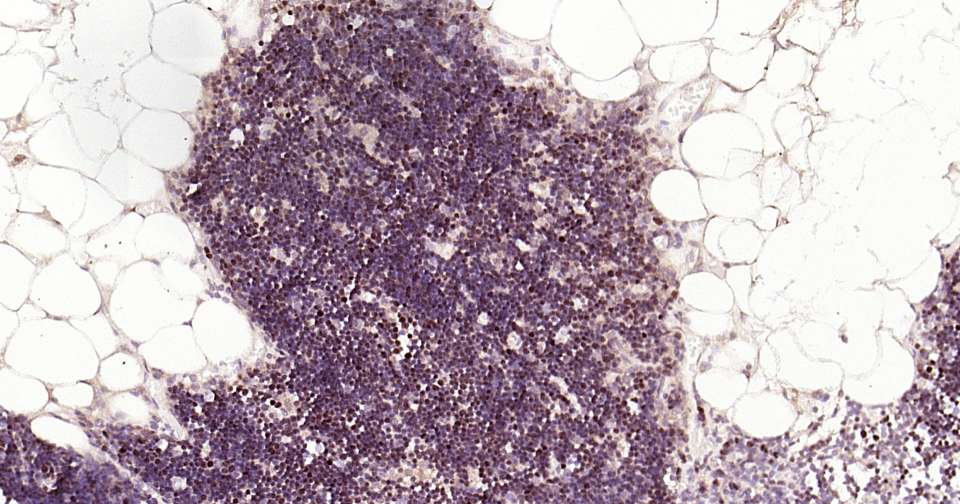

Immunohistochemical analysis of paraffin embedded mouse thymus tissue slide using IHC0328 (LEF1 Kit).

Immunohistochemical analysis of paraffin embedded human thymus tissue slide using IHC0328 (LEF1 Kit).

Immunohistochemical analysis of paraffin embedded rat thymus tissue slide using IHC0328 (LEF1 Kit).